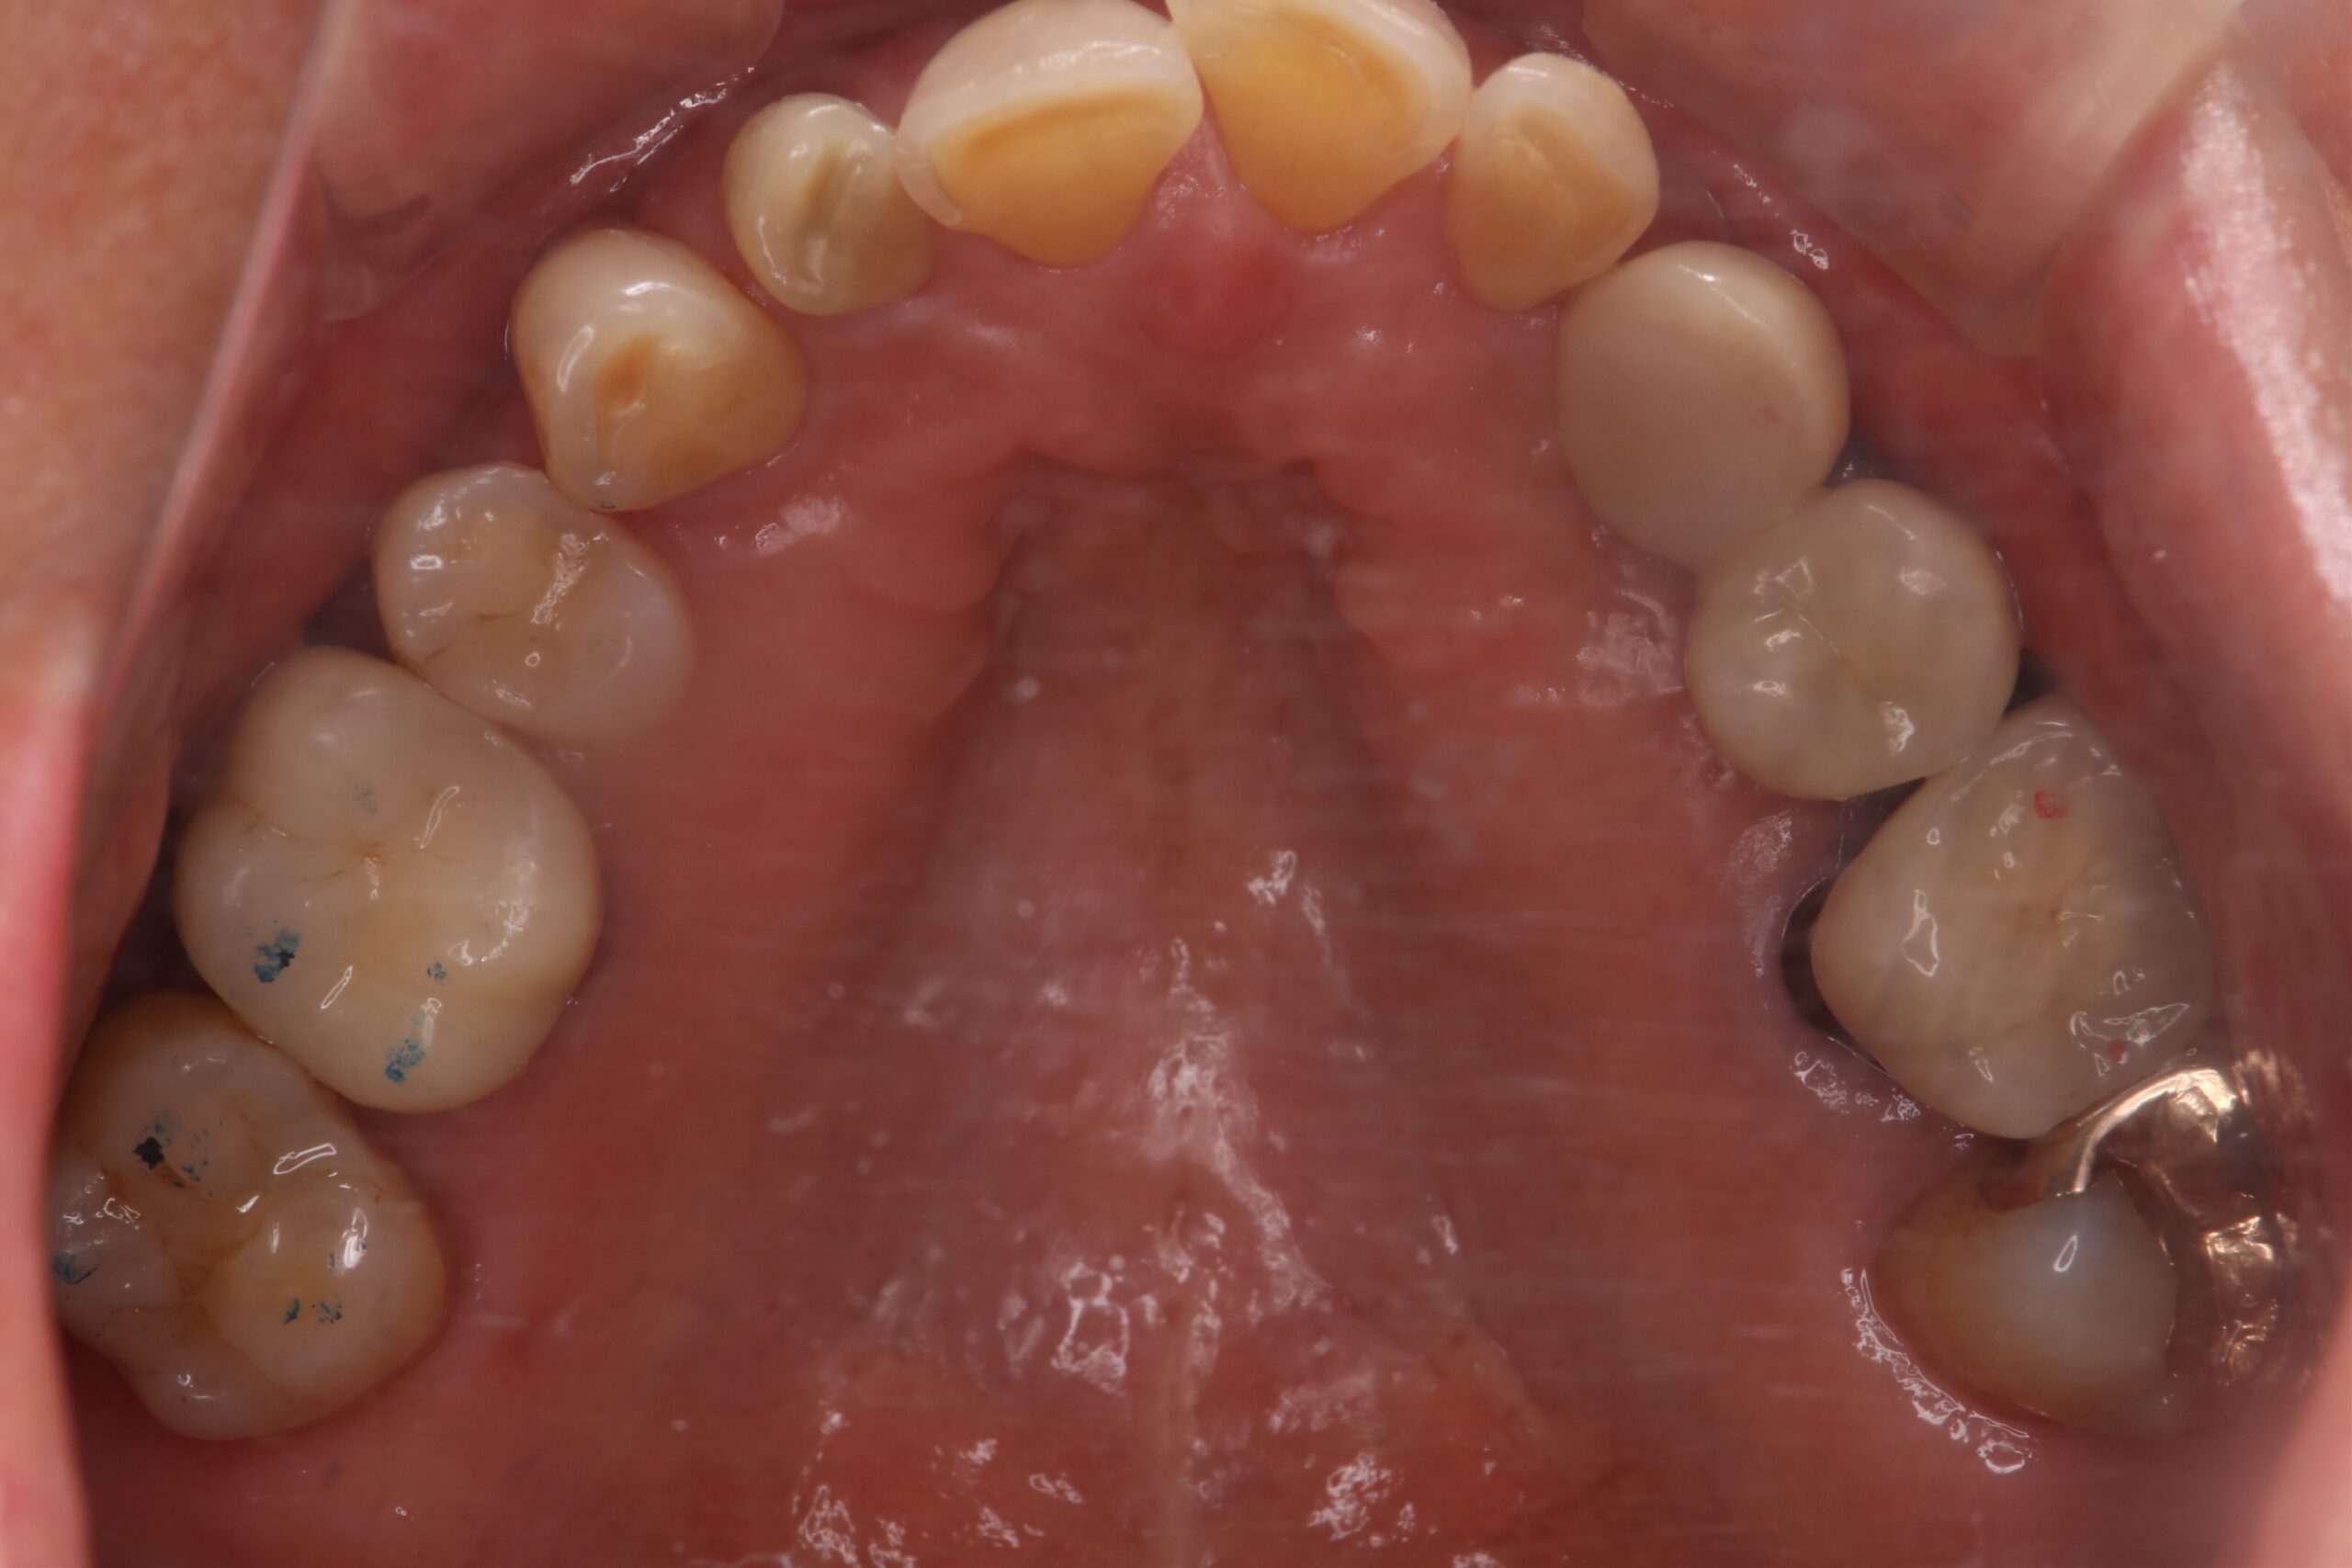

症例